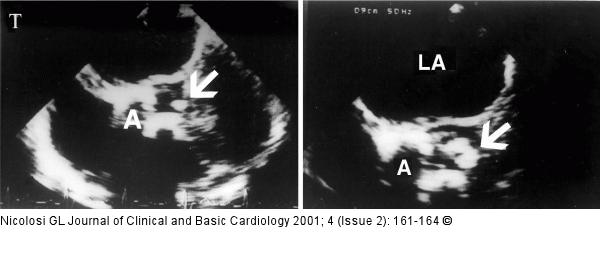

Figure/Graphic 4: Endokarditis - Diagnose - TEE Two short axis transoesophageal views, 15 days apart, from an elderly patient with calcific aortic valve and infective endocarditis. In the first examination (top) a vegetation could not be identified since the echogenic nodularities were indistinguishable from fibrocalcific deposits (arrow). In the second examination (bottom) a vegetation was diagnosed on the aortic valve for the evident increase in size of one of the nodularities (arrow) which was still not mobile in real time (see text). A= aortic valve; LA= left atrium |

Two short axis transoesophageal views, 15 days apart, from an elderly patient with calcific aortic valve and infective endocarditis. In the first examination (top) a vegetation could not be identified since the echogenic nodularities were indistinguishable from fibrocalcific deposits (arrow). In the second examination (bottom) a vegetation was diagnosed on the aortic valve for the evident increase in size of one of the nodularities (arrow) which was still not mobile in real time (see text). A= aortic valve; LA= left atrium |